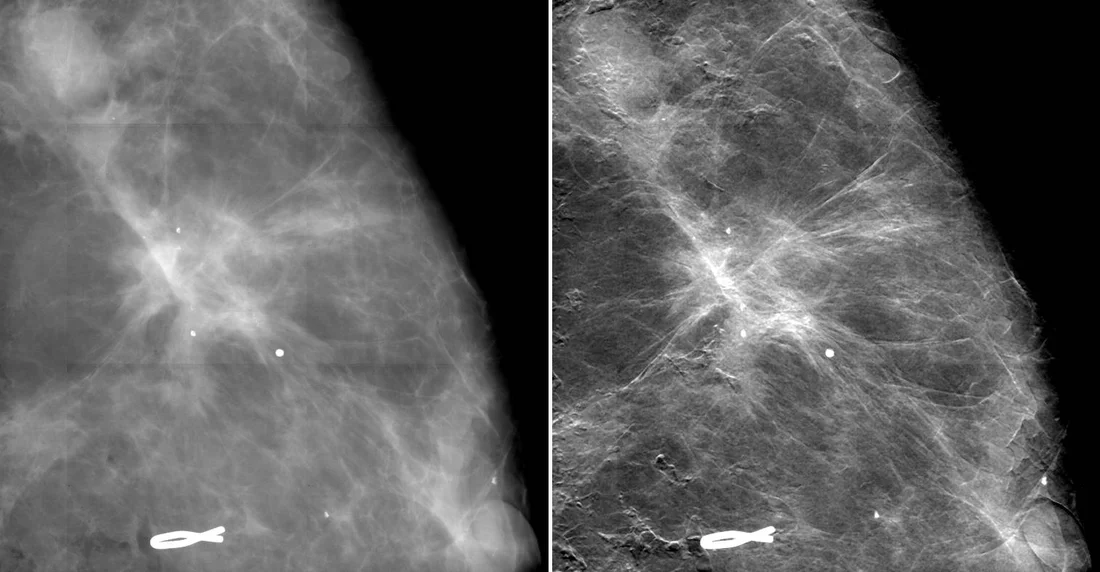

Der Vergleich von Röntgenaufnahmen von Brustgewebe mit einer konventionellen Mammografie sowie der neuen Mammografiemethode zeigt eine deutliche Verbesserung der Bildschärfe und damit der Sichtbarkeit der Ausläufer des Tumors (hell). Bild: Paul Scherrer Institut/Kantonsspital Baden

In einer Abbildung der weiblichen Brust mit dem neuen Verfahren wird die Abgrenzung zwischen Tumor und gesundem Gewebe deutlicher als bei der konventionellen Mammografie. Selbst die feinen Ausläufer der Wucherung sind klar zu erkennen. «Dies kann es in Zukunft ermöglichen, eine Operation besser vorzubereiten und den Eingriff genauer einzugrenzen», erklärt Nik Hauser, Leiter des Brustzentrums am Kantonsspital Baden. Auf den Bildern sind auch winzige, weisse Klümpchen zu sehen. Diese sogenannten Mikroverkalkungen geben je nach Grösse und Struktur Aufschluss über die Bösartigkeit einer Brustveränderung. Und da durch die gewonnene Bildschärfe bereits viel kleinere Strukturen dieser Art sichtbar werden, könnte mit der neuen Methode bereits die Erkennung von Brustkrebs in einem sehr frühen Vorstadium gelingen. «Dies wäre für die Praxis äusserst vielversprechend», sagt Hauser, denn, «je früher man eine verdächtige Gewebeveränderung erkennt und behandeln kann, desto höher sind die Überlebenschancen.»